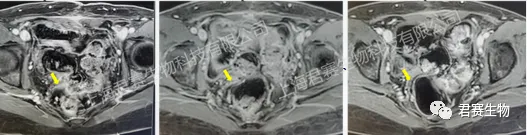

幸运的是,L女士经朋友介绍得知,君赛生物正在上海市第十人民医院开展GC101 TIL治疗复发/晚期妇科肿瘤的临床试验。在程忠平教授及十院妇科医护团队的密切配合下,L女士于2021年8月顺利接受了TIL细胞回输。出院后每次定期随访结果均显示肿瘤标志物持续降低,肿瘤持续缩小,治疗后两个多月各项检查指标便恢复正常水平。

令人欣喜的是,一位曾被确诊为IV期子宫内膜癌的患者L女士,继接受君赛生物GC101 TIL单次回输治疗后2个月,肿瘤病灶即完全消失,获得CR(完全缓解)疗效,至今已无瘤生存超4年,摆脱需长期服药和频繁辗转于各大医院带来的生理和心理上的煎熬,回归正常生活和工作的健康状态。